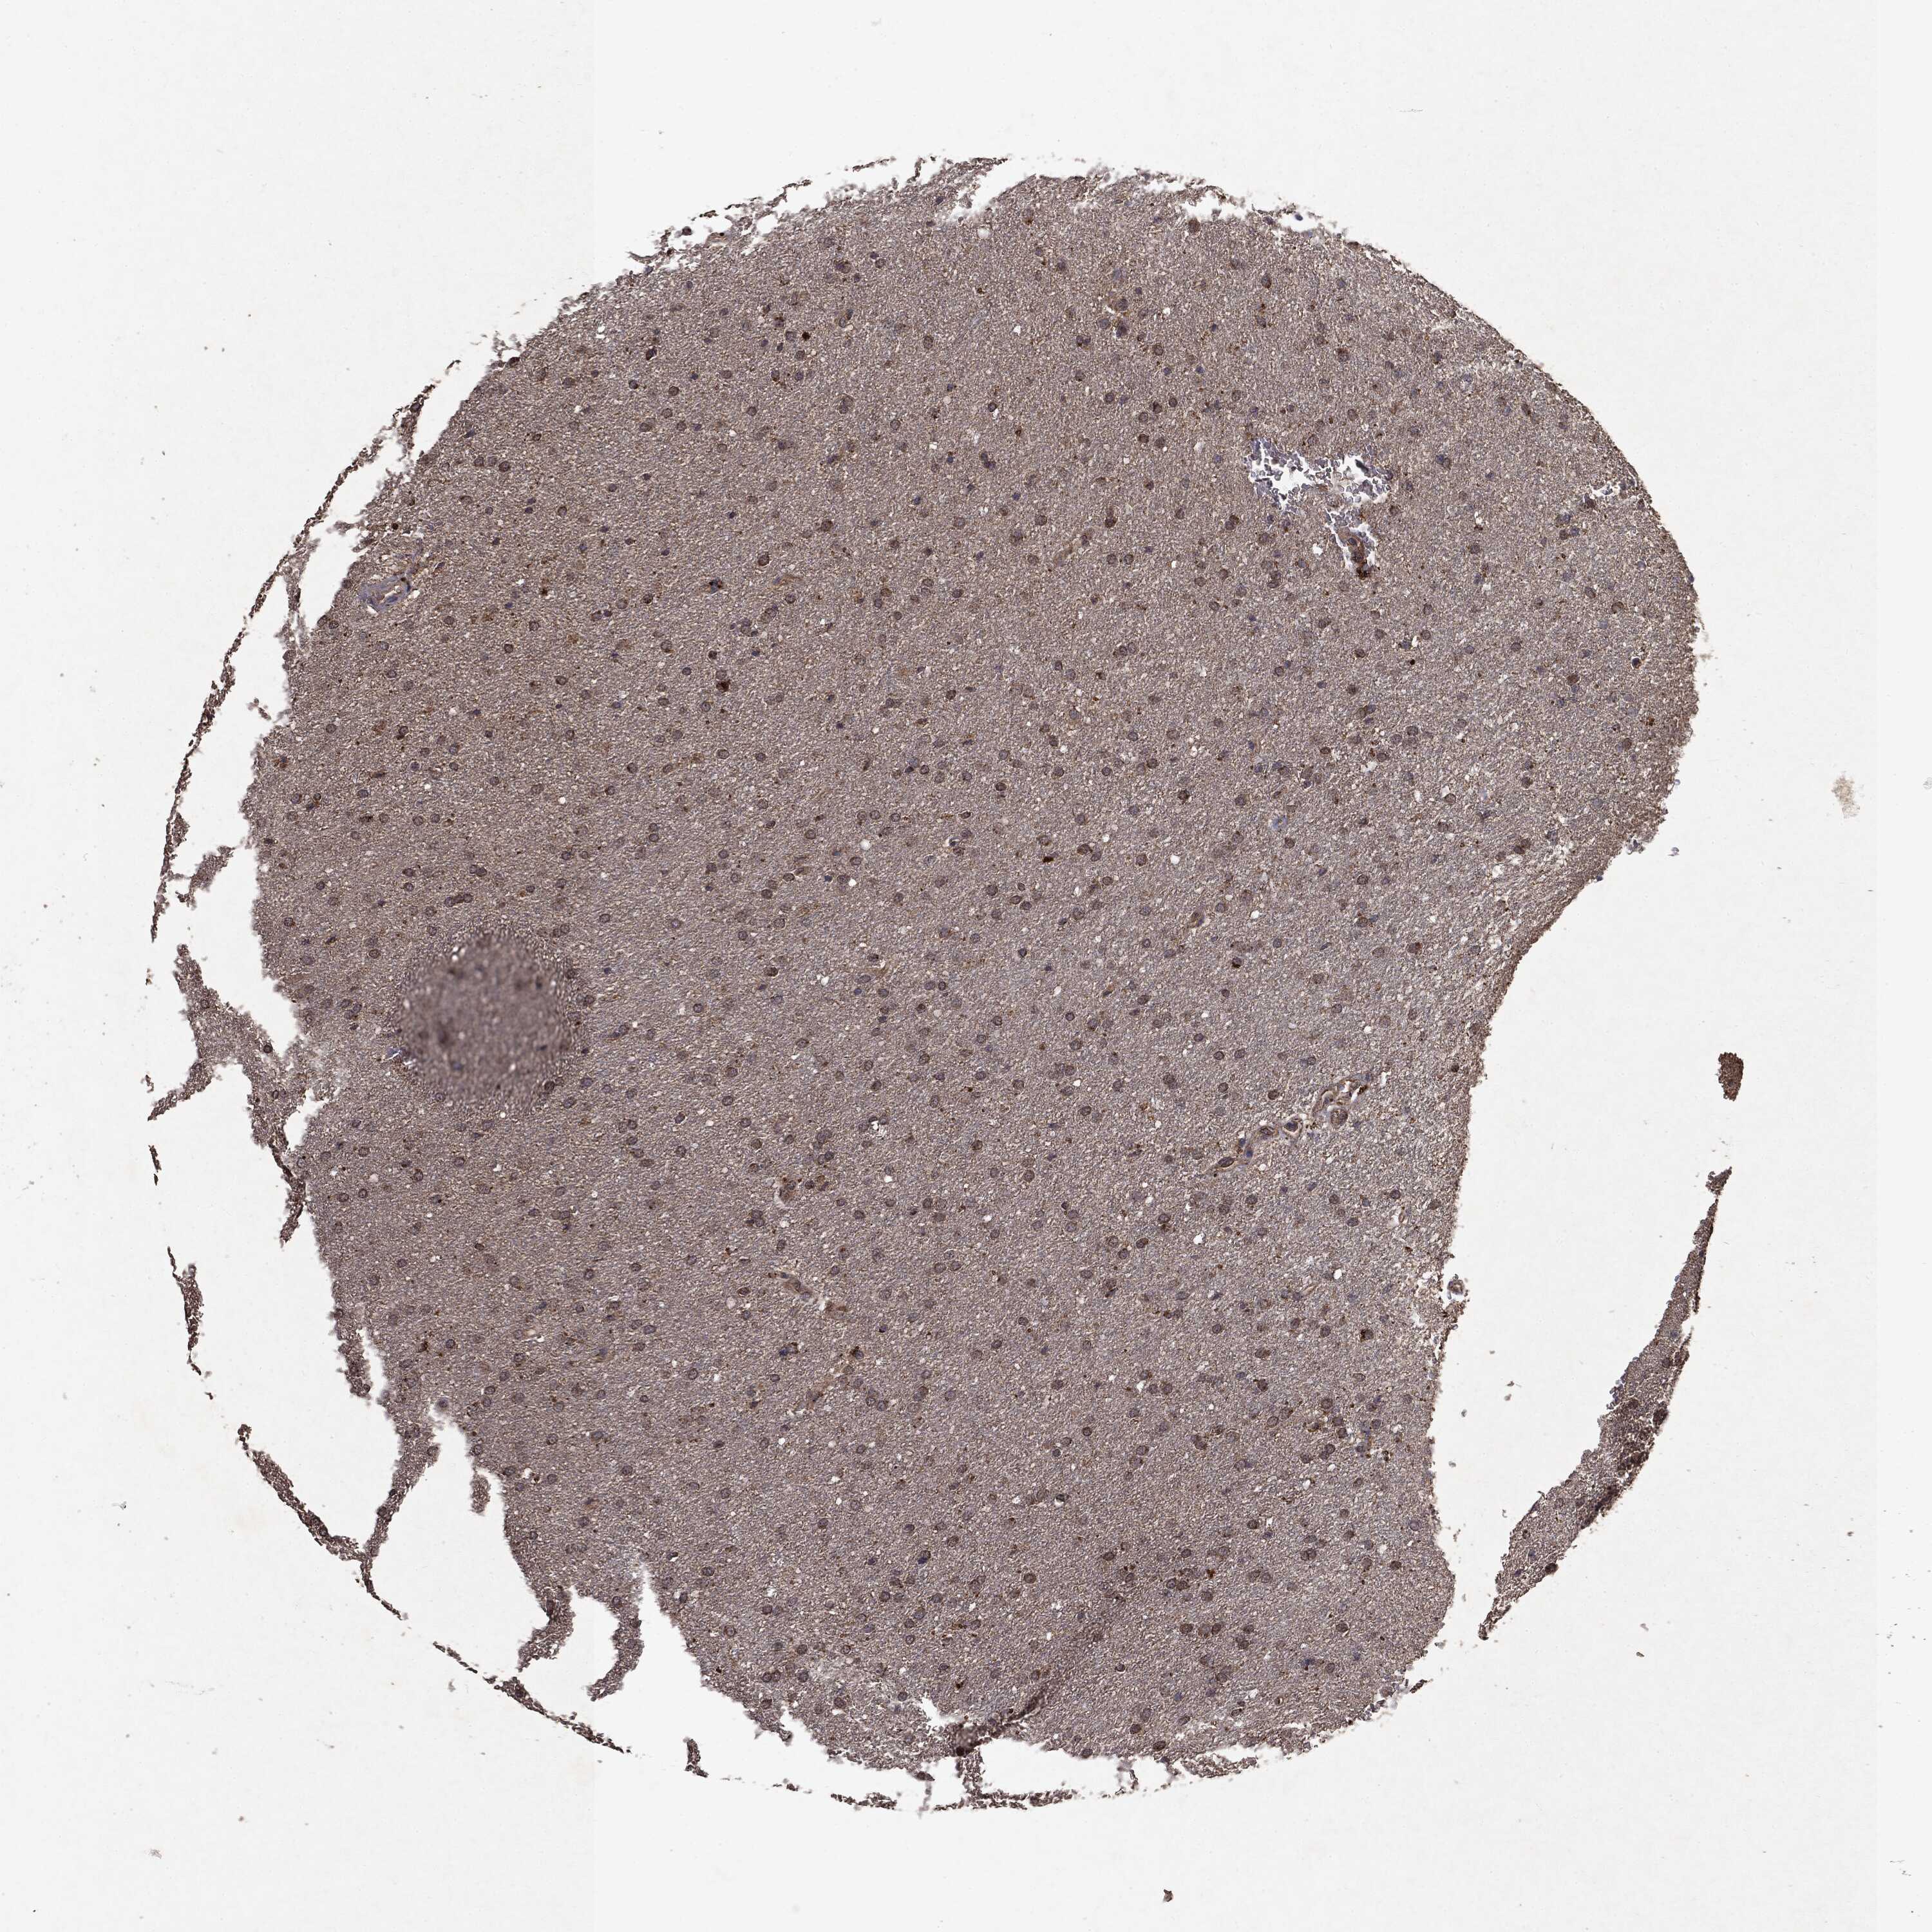

GLIOMA - Protein expressioni

A mouse-over function shows sample information and annotation data. Click on an image to view it in a full screen mode. Samples can be filtered based on level of antibody staining by selecting one or several of the following categories: high, medium, low and not detected. The assay and annotation is described here.

Note that samples used for immunohistochemistry by the Human Protein Atlas do not correspond to samples in the TCGA dataset.

Antibody stainingi

Antibody staining in the annotated cell types in the current human tissue is reported as not detected, low, medium, or high, based on conventional immunohistochemistry profiling in selected tissues. This score is based on the combination of the staining intensity and fraction of stained cells.

Each image is clickable and will lead to virtual microscopy that enables deeper exploration of all samples and also displays staining intensity scores, fraction scores and subcellular localization as well as patient and tissue information for each sample.

CAB069425

CAB080053

CAB080065

CAB080070

CAB080081

CAB080095

CAB080097

Staining

High

Medium

Low

Not detected

Intensity

Strong

Moderate

Weak

Negative

Quantity

>75%

75%-25%

<25%

None

Location

Nuclear

Cytoplasmic/membranous

Cytoplasmic/membranous,nuclear

Glioma, malignant, Low grade

Glioma, malignant, High grade

Glioma, malignant, NOS